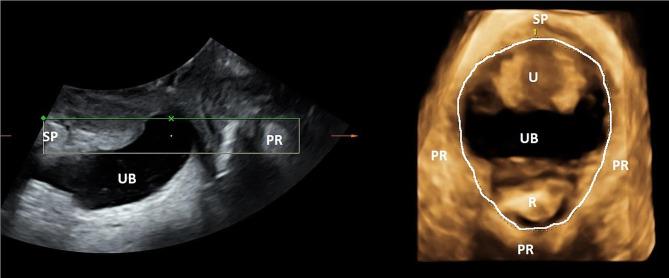

Cross sectional study of 10 professional opera singers examined with transperineal ultrasound in the supine position at rest and contraction, and standing at rest and during singing. Levator hiatal area was measured in a 3D rendered volume. Levator hiatal anteroposterior (AP) diameter and bladder neck distance from symphysis were measured in 2D images.

The AP diameter was shortened from supine rest to contraction (15 mm), standing (6 mm) and singing (9 mm), all p < 0.01. The bladder neck had a non-significant descent of 3 mm during singing. The mean proportional change in AP diameter from rest to contraction was 24.2% (moderate to strong contraction) and from rest to singing was 15% (weak to moderate contraction).

Transperineal ultrasound can be used to examine the PFM during singing. The classically trained singers had good voluntary PFM contraction and moderate contraction during singing. AP diameter was significantly shortened from supine to upright position, with further shortening during singing, confirming that female opera singers contracted their pelvic floor during singing.

对 10 名专业歌剧歌手进行横断面研究,在仰卧位休息和收缩时、站立位休息和歌唱时进行经会阴超声检查。在 3D 渲染体积中测量提肌裂孔区域。在 2D 图像中测量提肌裂孔前后(AP)直径和膀胱颈距耻骨联合的距离。

AP 直径从仰卧位休息缩短到收缩(15 毫米)、站立(6 毫米)和歌唱(9 毫米),所有结果均 P < 0.01。在歌唱期间,膀胱颈有 3 毫米的非显著下降。从休息到收缩的 AP 直径的平均比例变化为 24.2%(中度至强烈收缩),从休息到歌唱的比例变化为 15%(弱至中度收缩)。

经会阴超声可用于检查歌唱时的 PFM。受过古典训练的歌手具有良好的自愿性 PFM 收缩能力,在歌唱时具有中度收缩。从仰卧位到直立位,AP 直径显著缩短,在歌唱时进一步缩短,这证实了女性歌剧歌手在歌唱时收缩盆底。